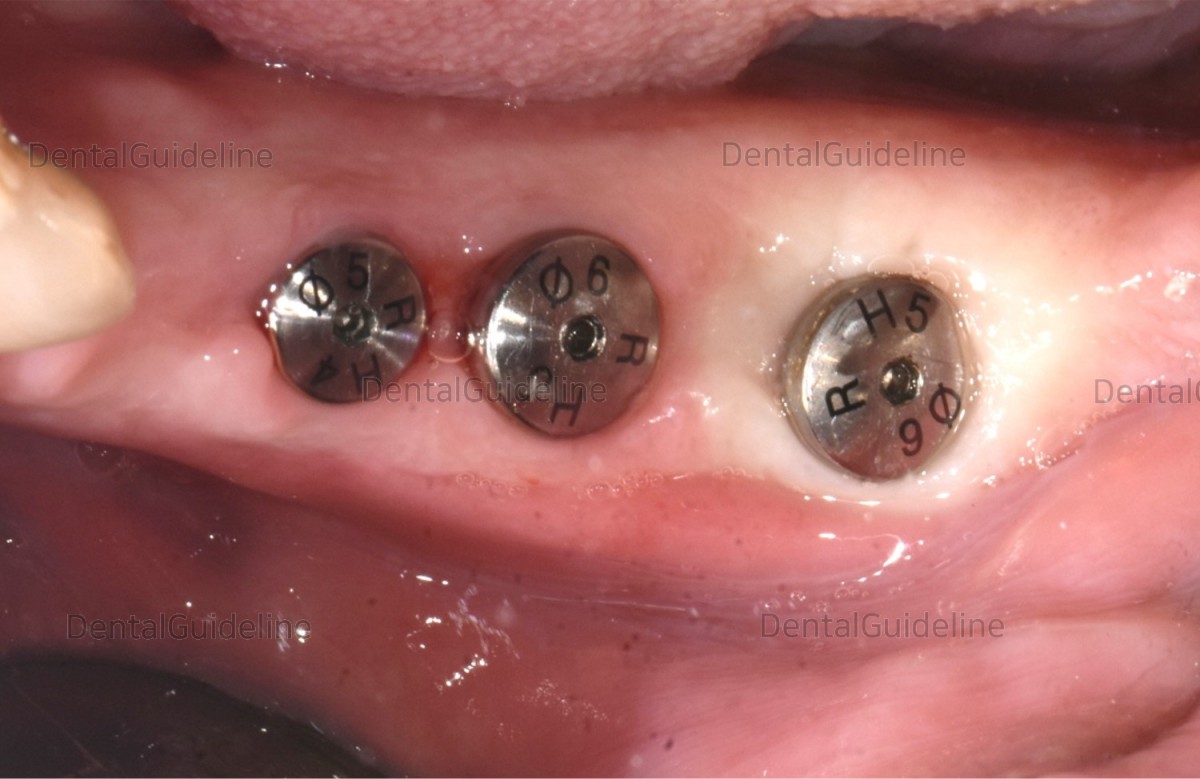

Healing Abutments were replaced

with those of other sizes to get the optimal form of the gingiva.

Re-measurement of ISQ at the 1st molar. In 3weeks, the value of ISQ was improved by 5.23%.